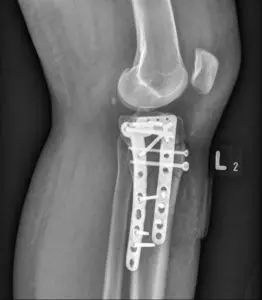

To technika obrazowania wykorzystująca promieniowanie rentgenowskie (promieniowanie X). Badanie rentgenowskie jest podstawową metodą obrazowania układu kostnego ze względu na szeroką dostępność, stosunkowo niskie koszty i krótki czas badania.

RTG, badanie rentgenowskie, zwane także potocznie prześwietleniem lub rentgenem, to technika obrazowania wykorzystująca promieniowanie rentgenowskie (promieniowanie X). Badanie rentgenowskie jest podstawową metodą obrazowania układu kostnego ze względu na szeroką dostępność, stosunkowo niskie koszty i krótki czas badania. RTG stosowane jest w medycynie już od ponad 100 lat, dzięki czemu jest to technika bardzo dobrze poznana i bezpieczna.

Na podstawie zdjęcia RTG ocenia się strukturę tkanki kostnej – np. ewentualne pęknięcia i złamania. U większości pacjentów z urazem kostnym dzięki badaniu rentgenowskiemu można zaplanować leczenie i kontrolować postępy gojenia. Rentgen nie nadaje się do oceny innych tkanek, czyli np. urazu więzadeł czy mięśni. Badanie RTG pokazuje jedynie zarys tkanek miękkich, a nie strukturę.